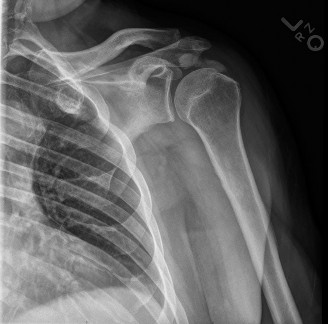

The correct answer is (A). In a young patient, the most likely injury associated with a glenohumeral dislocation is a labral tear (see Fig. 2–31). In an older patient, >40 years old, a rotator cuff tear is more likely. Other possible associated injuries include:

Figure 2–31 MRA demonstrating an anterior labral tear.

These all are less common than a labral tear. Each of these injuries need to be identified and treated appropriately at the time of surgery to ensure a satisfactory outcome.